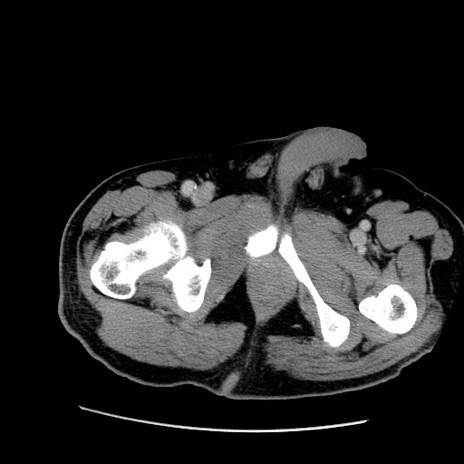

症例22(横断像)

【症例】50歳代男性

【主訴】腹痛

【現病歴】AVMからの被殻出血のため回復期リハ病棟入院中。 本日午後3時頃急に下腹部痛が出現した。

【既往歴】AVM、被殻出血、虫垂炎、高血圧

【身体所見】意識晴明、左半身不全麻痺、会話の理解は良好、36.5°C、腹部:膨隆、全体に板状硬、下腹部正中に圧痛点あり、反跳痛-、筋性防御不明、右下腹部にope scar

【データ】WBC 9400、CRP 0.06